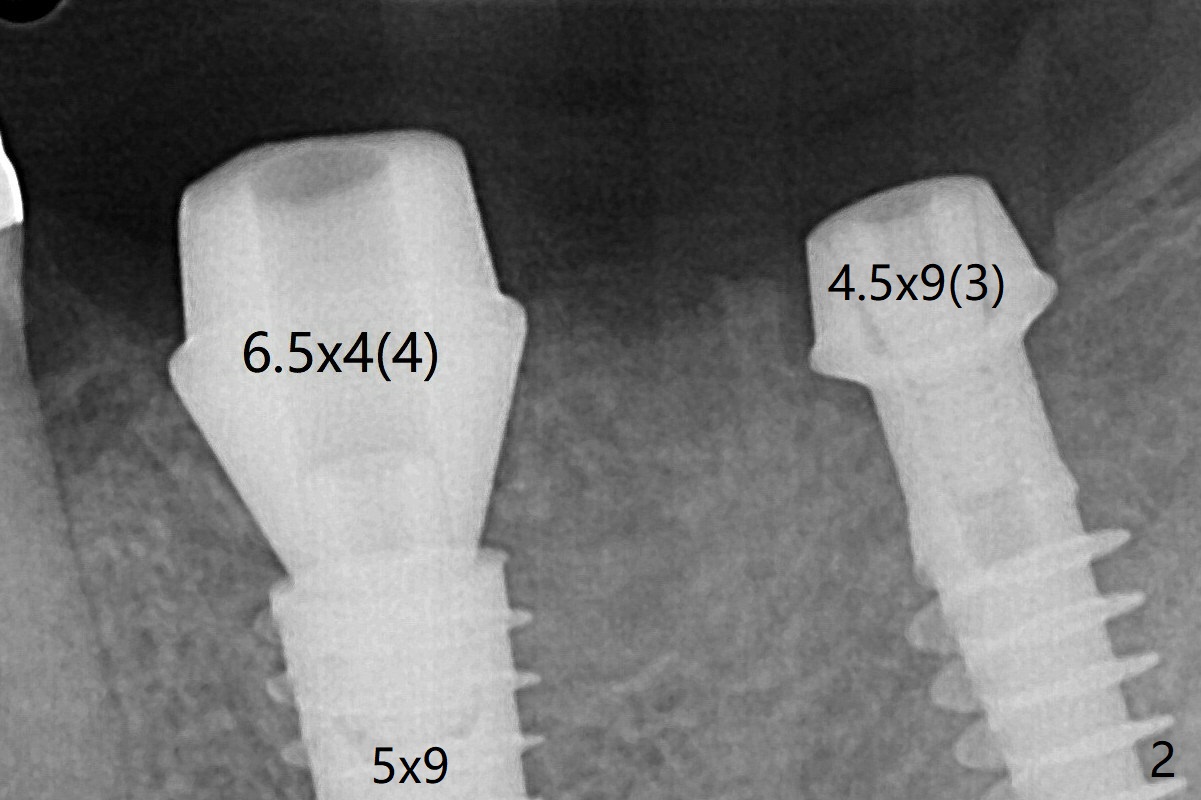

Because of supraeruption of the opposing teeth, the abutment at #19 is heavily reduced, whereas the Magicore is placed super low (Fig.2).  The latter may be backed up or crown lengthening is necessary.  In fact neither is necessary, since there is crestal bone loss at #18 nearly 3 months postop (Fig.3).  There is no difficulty in placing 4.5 mm healing cuff.